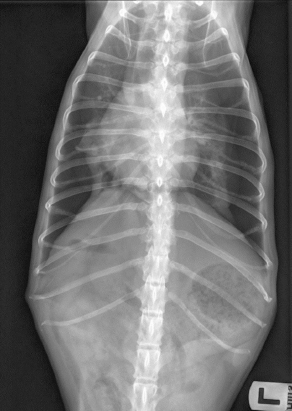

Orthogonal radiographs confirmed proper tube placement as well as the absence of etiological findings. Recovery from anesthesia was uneventful. The patient remained in the intensive care unit under strict surveillance for recurrent dyspnea and further medical treatment, including continuous intravenous fluids using a balanced crystalloid solution (40 ml/kg/24 hours, Sterofundin ISO®, B.Braun Melsungen AG, Melsungen, Germany), intravenous buprenorphine (0.02 mg/kg q8h, Buprenovet 0.3 mg/ml, Elanco Germany, Bad Homburg, Germany) and metamizole (40 mg/kg q8h, Novacen 500 mg/ml, cp-pharma, Burgdorf, Germany).

Fig. 3. Radiographic image of the thorax in latero-lateral view with the dog laying on the left side. Bilateral chest tubes are placed at the level of the 8th intercostal space. No etiological findings for pneumothorax are visible and the thorax is completely evacuated from air. The endotracheal tube is visible at the level of the thoracic aperture.